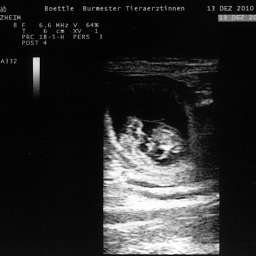

Bild von Wilmas Ultraschalltermin

13.12.2010, 32. Tag: Heute 9.15 Uhr wurde uns ein überwältigendes Erlebnis zuteil: Beim Ultraschall durften wir sehen,

daß Wilma 5 kleine Wunder unter ihrem Herzen trägt. Wir konnten ganz deutlich Herztöne, Kopf und Körper, Augen, Nabelschnur, Bewegungen und gesunde Fruchthüllen erkennen.

Wir danken Wilma für ihr warmes Geschenk und sind sehr, sehr gerührt!!! Obwohl äußerlich an ihrem Bauch nichts zu erkennen ist,

haben die Fruchthüllen schon eine unglaubliche Größe von ca. 3-4 cm.

Der errechnete Gebutstermin ist der 13. Januar 2011.Vielen Dank für die vielen Mails mit den guten Gedanken und Wünschen.

Alle 5 Ultraschallbilder können in unserer FOTOGALERIE einzeln angeklickt und damit vergrößert betrachtet werden!